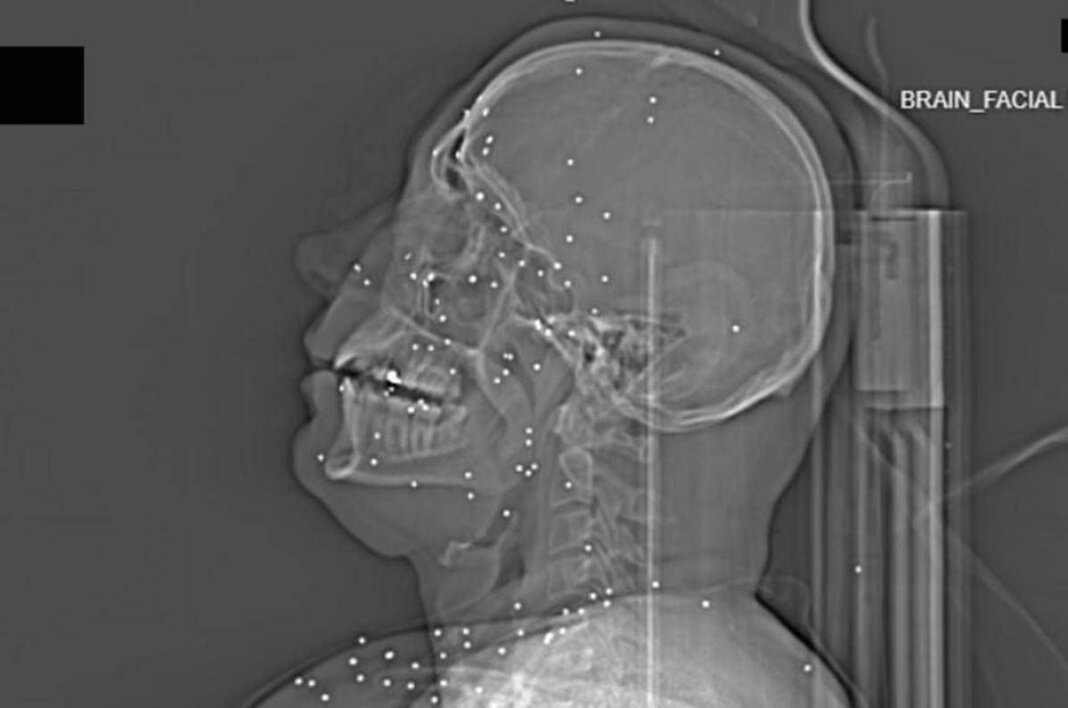

Il volto di Anahita – nome di fantasia, poco più che ventenne – appare come un cielo notturno attraversato da punti luminosi. Piccole sfere metalliche, da 2 a 5 millimetri, disseminate sul viso, nelle orbite oculari, persino nella massa scura del cervello. Sono proiettili “birdshot”, pallini da caccia sparati da un fucile a pompa. A distanza ravvicinata, spiegano gli esperti, non sono affatto “meno letali”: possono frantumare ossa, devastare tessuti molli, perforare facilmente un bulbo oculare. Anahita ha perso almeno un occhio, forse entrambi.

Quell’immagine non è un caso isolato. Fa parte di oltre 75 set di esami diagnostici provenienti da un singolo ospedale di una grande città iraniana, raccolti nel corso di una sola serata, durante la stretta repressiva di gennaio. Una concentrazione temporale che, già di per sé, racconta una dinamica da “mass casualty”, evento con numerose vittime simultanee, tipico degli scenari di guerra o dei grandi disastri.

Accanto ai colpi di grosso calibro, emerge con forza un altro elemento: l’uso sistematico dei pallini metallici. L’Iran è tra i pochi Paesi in cui le forze di sicurezza impiegano birdshot metallico. A lunga distanza, i pallini si disperdono e colpiscono indiscriminatamente. A distanza ravvicinata, diventano devastanti: decine, talvolta centinaia di micro-proiettili che penetrano simultaneamente nei tessuti.

Le radiografie raccontano questa brutalità in modo quasi didascalico. Il torace di Ali – anche qui, nome di fantasia – contiene oltre 174 pallini metallici concentrati nella cavità destra. Il polmone parzialmente collassato, circondato da sangue e gas. Secondo gli esperti consultati, anche con un intervento chirurgico immediato e massiccio, il rischio di morte rimane altissimo.

Ma non è solo la gravità delle ferite a colpire. Caso dopo caso, le immagini mostrano corpi colpiti al volto, al torace, ai genitali. Ventinove pazienti risultano feriti al viso da birdshot. Almeno nove presentano lesioni nell’area genitale o pelvica, provocate sia da pallini sia, in alcuni casi, da fucili ad alto calibro.